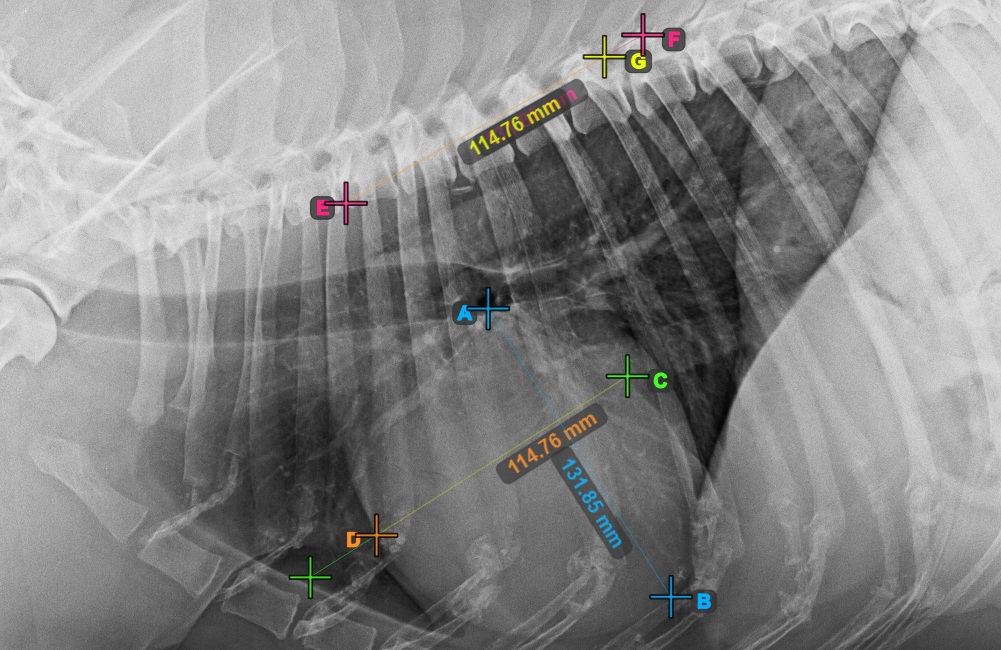

A VHS (Vertebral Heart Score) egy olyan mérés, amelyet állatorvosi gyakorlatban használnak a páciens szívének méretének és egészségének felmérésére. Válassza a VHS Szívmérés opciót a Komplex mérések menü alatt, és rendelje hozzá a bal egérgombot.

A VHS-mérés a szív méretét hasonlítja össze a gerinc csigolyáinak méretével, hogy meghatározza és jelezze a páciens esetleges szív- vagy keringési rendellenességeit.

Fejezze be a szív hosszanti tengelyét az Apex pont megjelölésével, a szív alsó részéhez közel.

Folytassa a mérést a szív rövid tengelyének legszélesebb jobb (feji) pontjának megjelölésével.

Fejezze be a szív rövid tengelyét a legszélesebb bal (caudal) pont megjelölésével.

Azonosítsa a T4 csigolya kezdetét (a gerinc negyedik csigolyatestét), a gerinc kezdőpontjától számítva. Jelölje meg a T4 csigolya kezdetét a mérés folytatásához. A szoftver a megjelölt pontból vonalakat húz a gerinc mentén. A vonalak hossza a szív mért hossz- és rövidtengelyétől függ.

A szükséges VHS-kalkulációk elvégzése előtt győződjön meg róla, hogy a vonalak pontosan a csigolyák mentén helyezkednek el.

Számolja meg a csigolyák számát a gerinc rövid tengelyét jelző vonal mentén. Adja meg a szükséges csigolyaszámot a Csigolyák száma mezőben a komplex mérési mód eszköztárában.

Nyomja meg a VHS pontszám számítása gombot a VHS-méréshez szükséges számítások elvégzéséhez. A VHS-pontszám megjelenik a komplex mérési mód eszköztárában. Ezenkívül a VHS-pontszám fel lesz tüntetve a képen is, a mérés részeként.